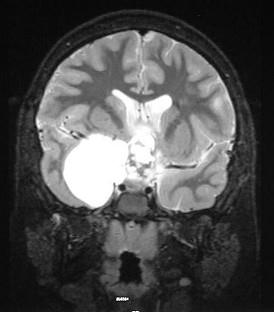

问题 下面哪一项肯定不是颅咽管瘤(见图)鉴别诊断疾病()

选项 A.垂体腺瘤 B.鞍结节脑膜瘤 C.鞍部异位松果体瘤 D.鞍部上皮样囊肿 E.三叉神经鞘瘤

答案 E